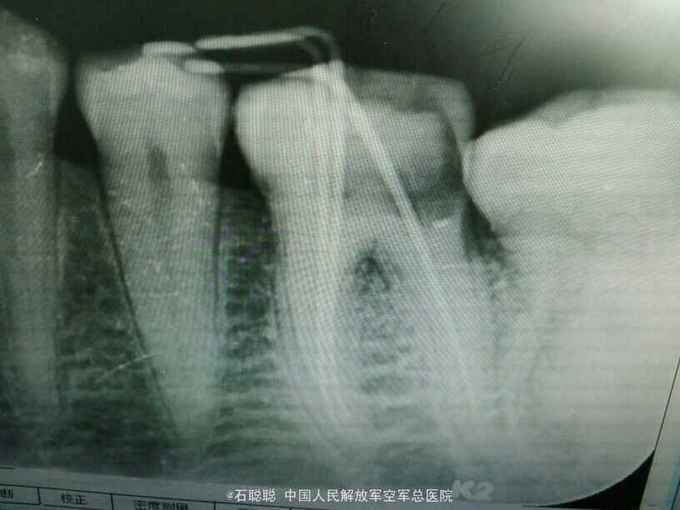

诊断:左下6急性牙髓炎 治疗计划:左下6根管治疗后冠修复 处置:左下6利多卡因局麻下开髓,揭顶,探及近颊,近舌,远中3个根管口,冲洗,干燥,置失活剂,氧化锌暂封 一周后复诊 诉无不适,检查左下6氧化锌暂封完整在位,叩痛-,不松动,牙龈未见异常 处置:左下6去除氧化锌暂封,测工作长度,近颊=18mm,近舌19mm,扩大至30#,远中=20mm,扩大至35#,冲洗,干燥,置CP棉球,氧化锌暂封 一周后复诊:左下6叩痛-,不松动,氧化锌完整在位 处:去除左下6氧化锌暂封,试主尖,冷侧压充填,氧化锌暂封 医嘱:一周后修复左下6